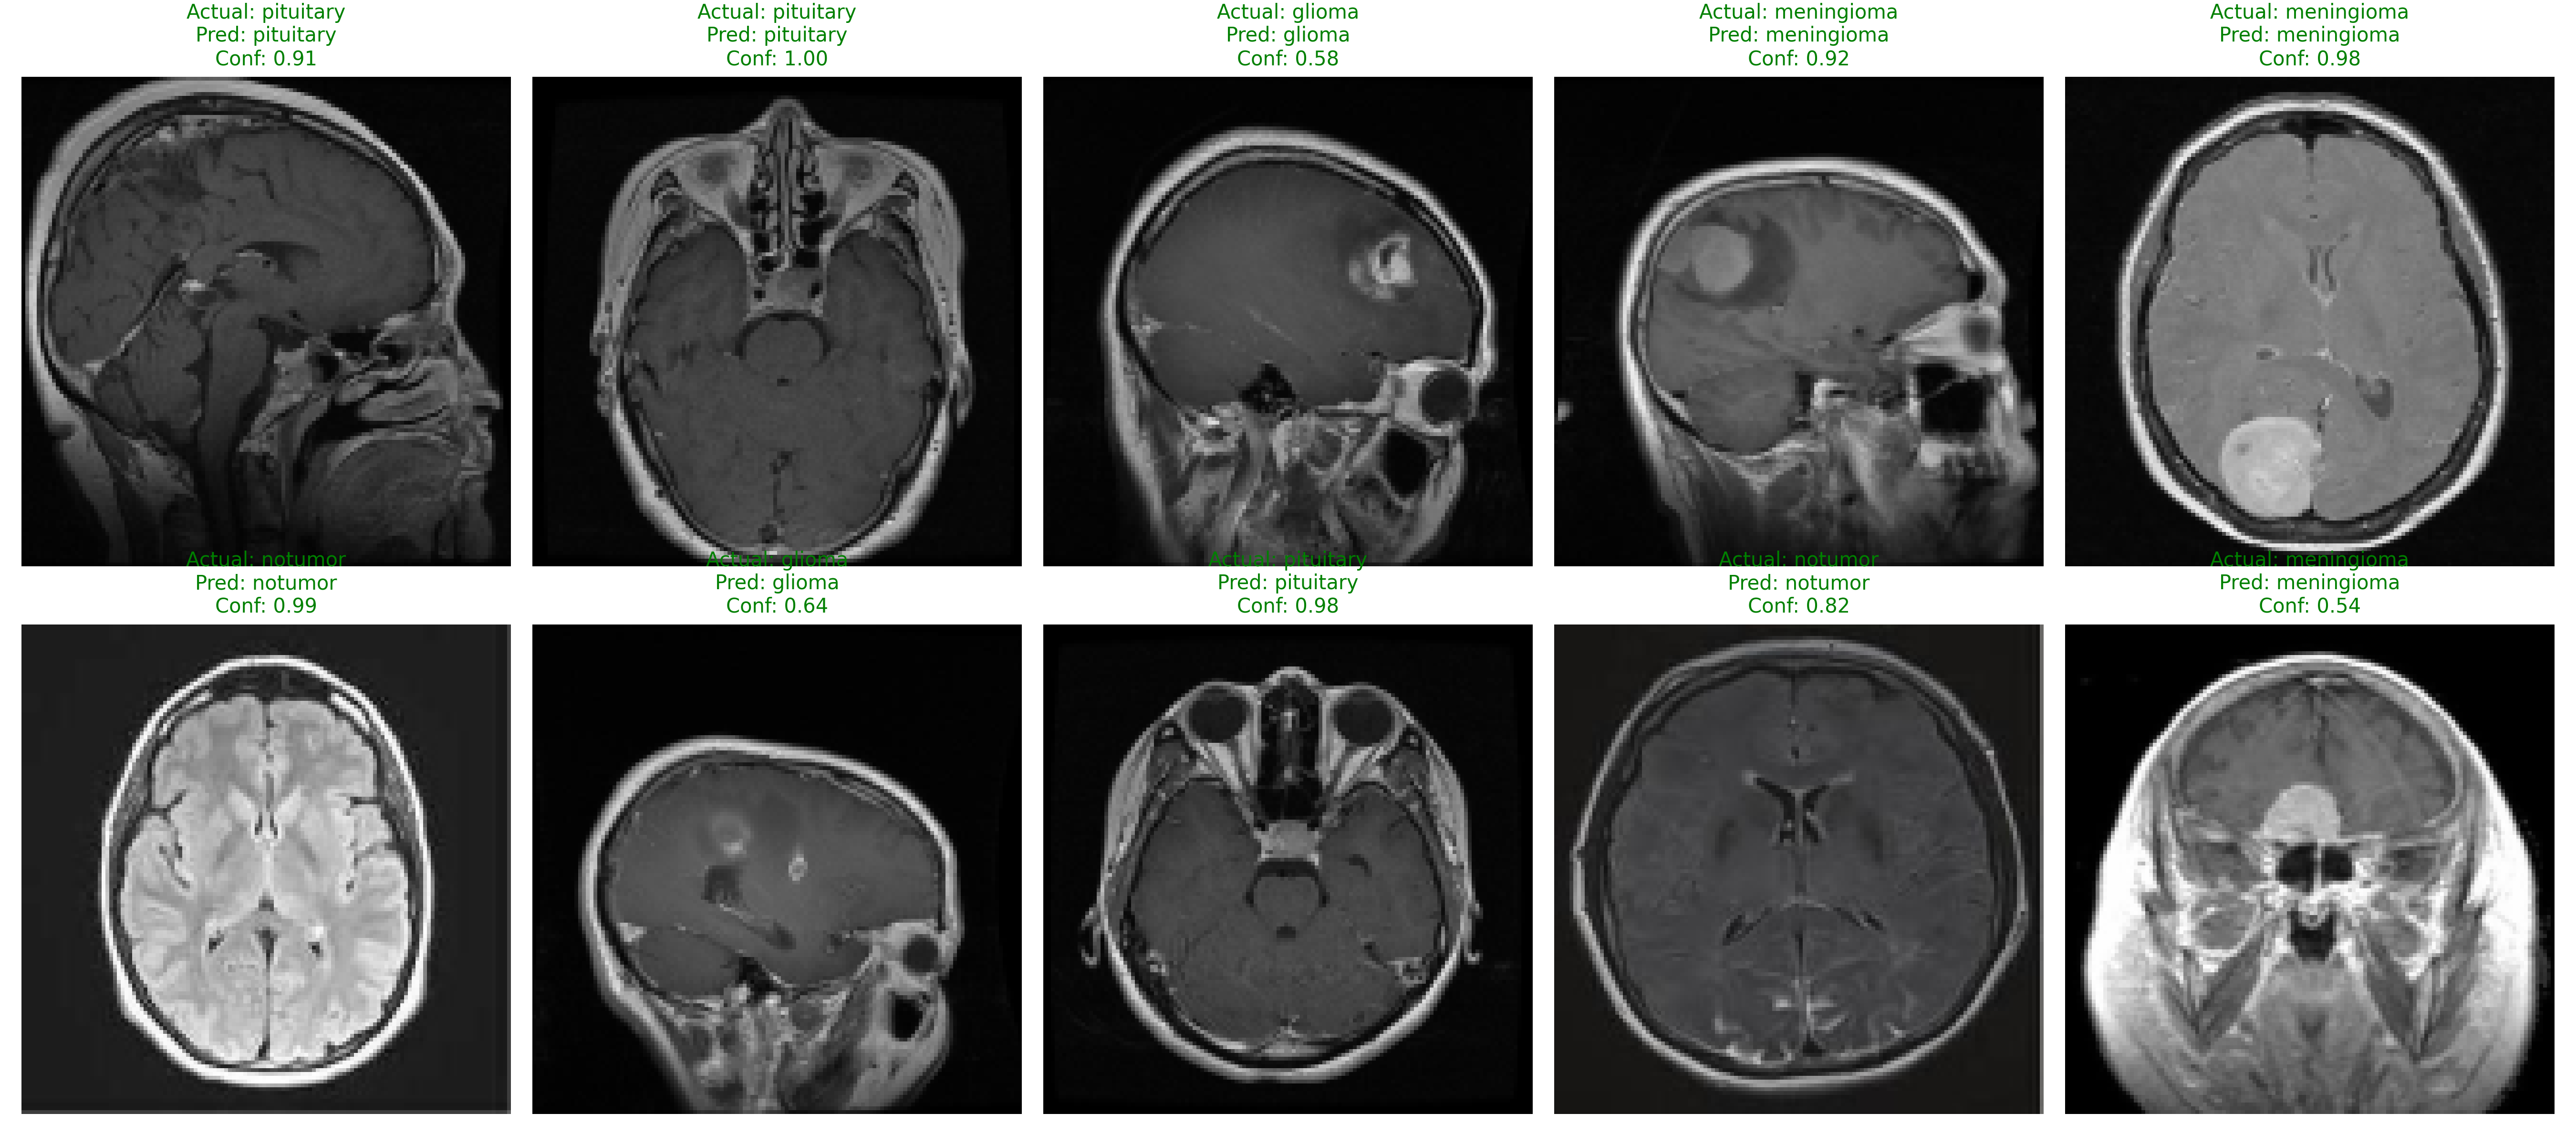

Critical Confusion Insight

Evaluation identifies Glioma (70% recall) as the primary clinical challenge. The Confusion Matrix reveals 45 Gliomas were misclassified as Meningiomas.

Implement multi-view T1/T2 weighted analysis to improve Glioma differentiation.

Diagnostic Confusion Map

N=656 Matrix

Diagonal intensity confirms correct identifications; externalized for optimized deployment.